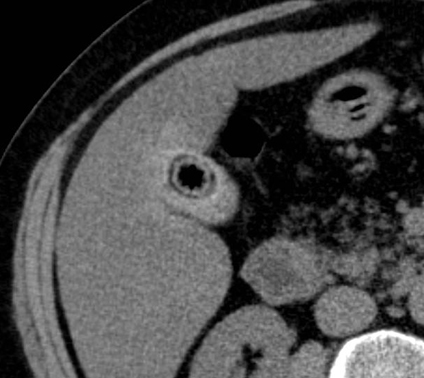

Calcul

vesiculaire de type pigmentaire en coupe

TDM axiale a non contrast . Forme arrondie a contour

calcique hyperdense et radiolucence a hypodense

centrale . La vesicule biliaire est pres isodense

avec le foie |

Image radiologique TDM en

coupe axiale de contrast intra veineuse . Calcul

pigmentaire de la vesicule biliaire , le foie en

contrast est hyperdense que la vesicule biliaire ,

paroie de la vesicule et canall cystique se en

voyant nette |